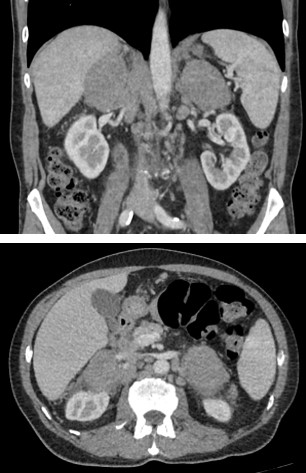

A 73-year-old man with no relevant past medical history and with complaints of asthenia, fever and weight loss over the past few months was referred for abdominal computer tomography after an incidental adrenal mass was detected on abdominal ultrasound. The CT scan (figure 1) revealed bilateral large solid adrenal masses with well-defined margins, homogeneous density and discrete contrast enhancement. Several enlarged paraaortic lymph nodes were also noted. Posterior laboratory studies revealed anemia and elevated LDH and β2-microglobulin. An ultrasound-guided biopsy of the left adrenal mass was performed revealing diffuse large B-cell lymphoma.

Its radiological appearance6,12,13 is non-specific and variable, appearing on CT as bilateral (about 70% of cases) solid, large and well-defined adrenal masses that may be hypovascular or have mild to moderate enhancement and that are not associated with calcifications. Similarly to our case, there may be involvement of other structures such as adjacent lymph nodes, emphasizing that for the diagnosis of PAL, the adrenal lesions must be the most prominent ones. On PET-CT these are metabolically active presenting avid glucose uptake.